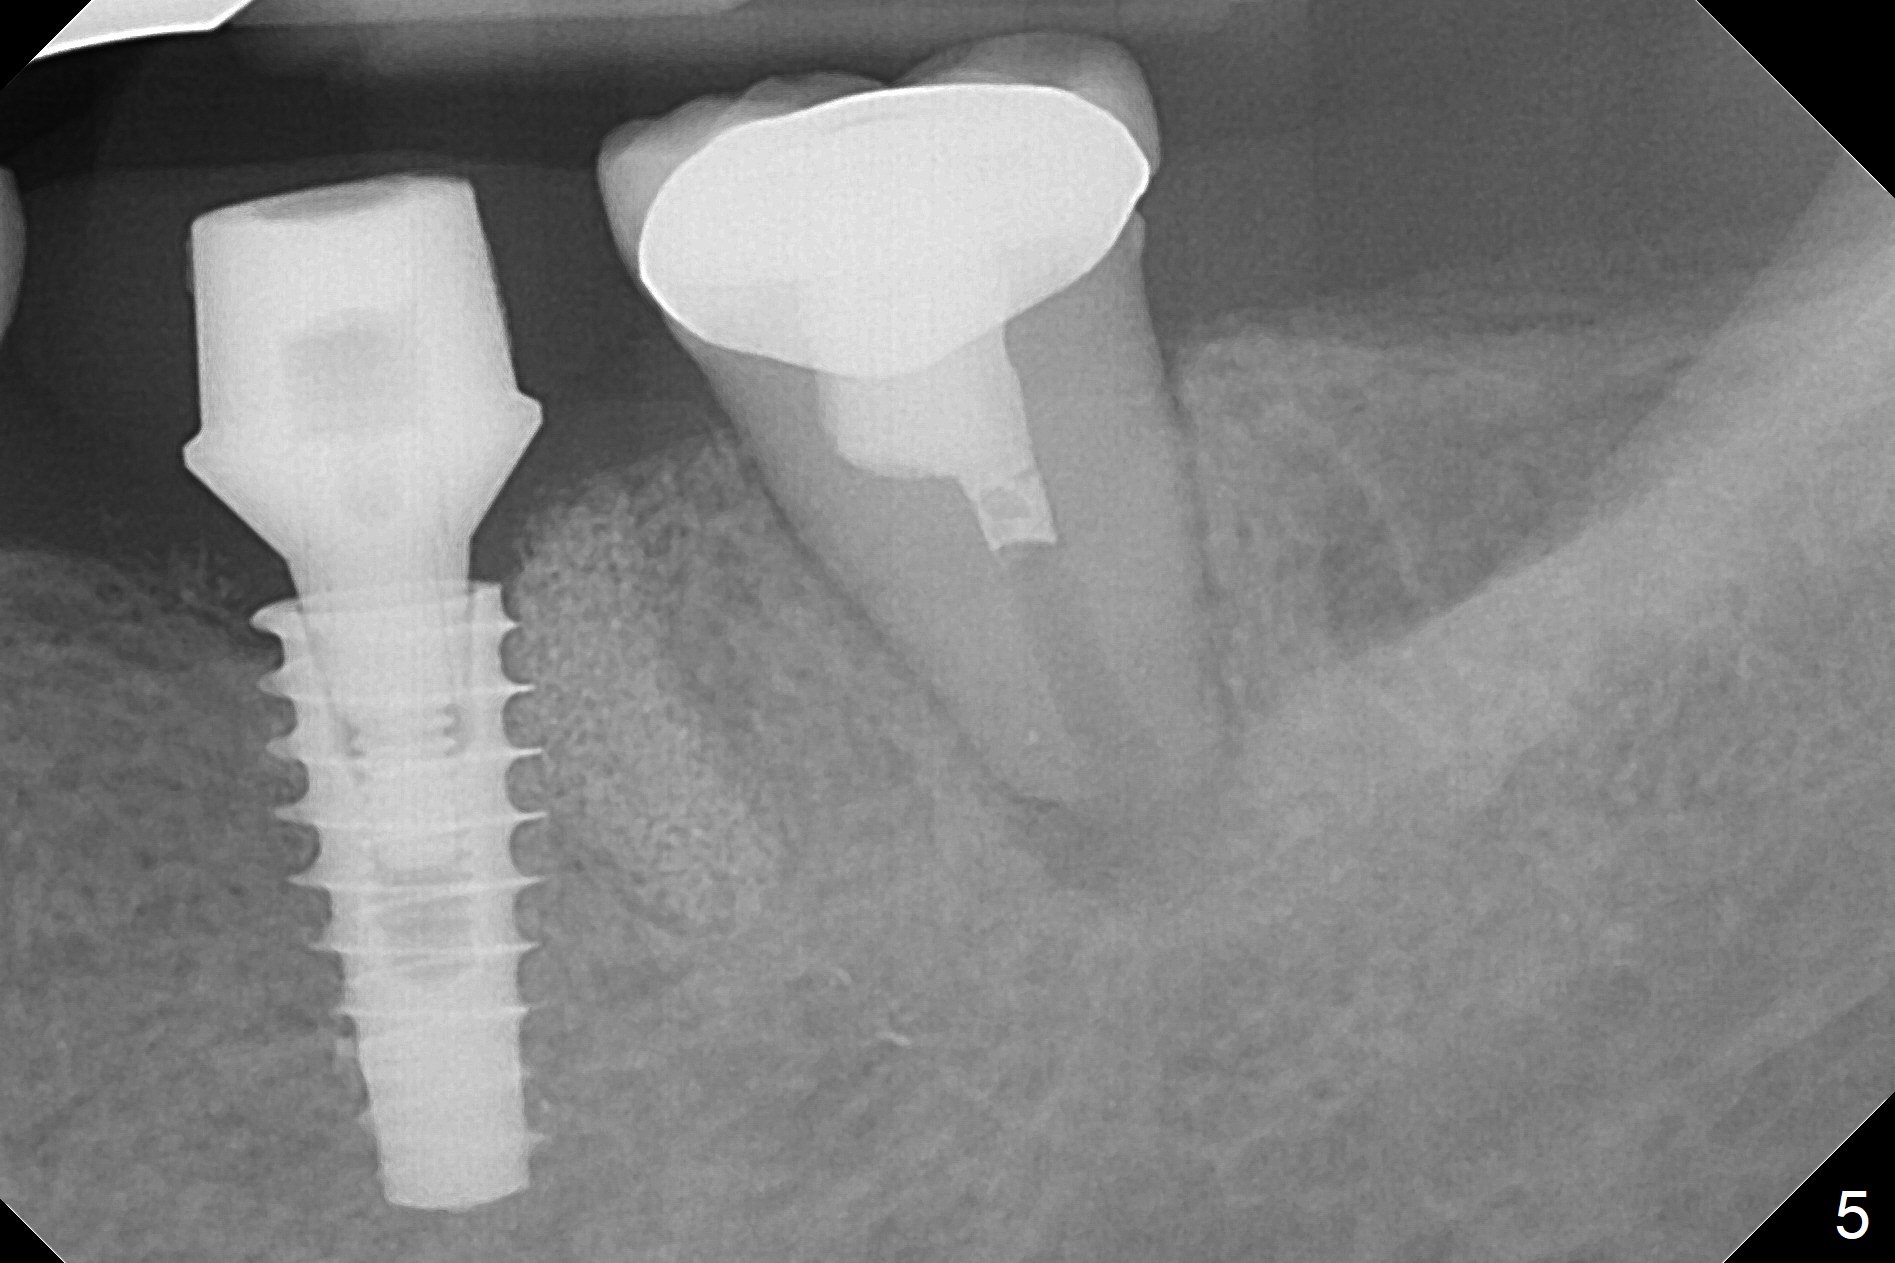

After making a 10 mm incision at the site of #19, #15c blade is used as an osteotome to start bone expansion, followed by Magic Split and Magic Expander (ME, 3 mm in diameter). The depth is approximately the bottom of the mesial socket. The osteotomy beyond the socket has to be done with 1.6 mm pilot drill (Fig.1) in combination of ME. Following ME 4.3 mm and Magic Drill (MD) 3.8 mm for 15 mm (gingival level), a 4.5x11 mm dummy implant is placed with 50 Ncm (Fig.3); the implant looks narrow for the edentulous space. After ME 4.8, MD 4.3 for 13 mm and Final Drill for 15 mm, a 5x11 mm IBS is inserted with >50 Ncm (Fig.3). With 2 more turns of the implant, a 6.5x4(2) mm abutment is placed (Fig.4). Periodontal dressing is applied around the abutment for additional retention. A provisional is fabricated 3 weeks postop. The provisional and abutment are loose 4 months postop (Fig.5). After retightening the abutment, impression is taken for final restoration. There is no bone loss 1 year 3 months post cementation (Fig.6). After use of #100 file (Fig.7), the canal is debrided with #140 file with 1.5 mm shorter in working length with placement of Calcium Hydroxide paste. Pain gets worse post RCT retreatment. There is limited native bone for primary stability when an immediate implant is placed (red dashed line: the superior border of the Inferior Alveolar Canal). Prepare IS regular and extra wide kits and tissue-level implants (>5 mm). Socket preservation may be done instead. If the socket is large and the vein is not so small, prepare PRF. In fact blood drawing fails. When the tooth is extracted, it is sensitive to remove granulation tissue. Socket preservation is done with Vanilla graft at #18 (Fig.8); there is ~3.5 mm bone between the bottom of the single socket and the Inferior Alveolar Canal (red dashed line). The socket at #18 seems to have healed 4 months post extraction (Fig.19), but the bone height appears to have been reduced (compare Fig.10,11). The buccolingual width is also decreased (Fig.12,13). A 4.5 or 5.0x10 mm implant is appropriate for the site (Fig.14). There is no bone loss at #19 (which may be associated with the bone expansion) 1.5 years post cementation (Fig.15). Therefore the osteotomy at #18 will be assisted with bone expanders after 2.2 mm drill.